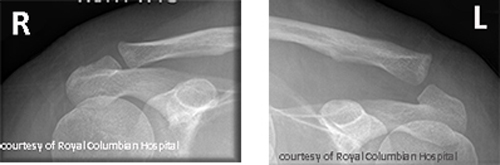

Which shoulder dislocation is more common and what causes it?

Anterior dislocation; caused by external rotation and abduction (e.g., fall or sports).

What is a Hill-Sachs lesion?

Compression fracture of the humeral head during anterior dislocation.

What causes posterior shoulder dislocations?

Seizures, electrocution, or axial load in internal rotation.

What are complications of shoulder dislocations?

Recurrent instability, Hill-Sachs lesions, arthritis.